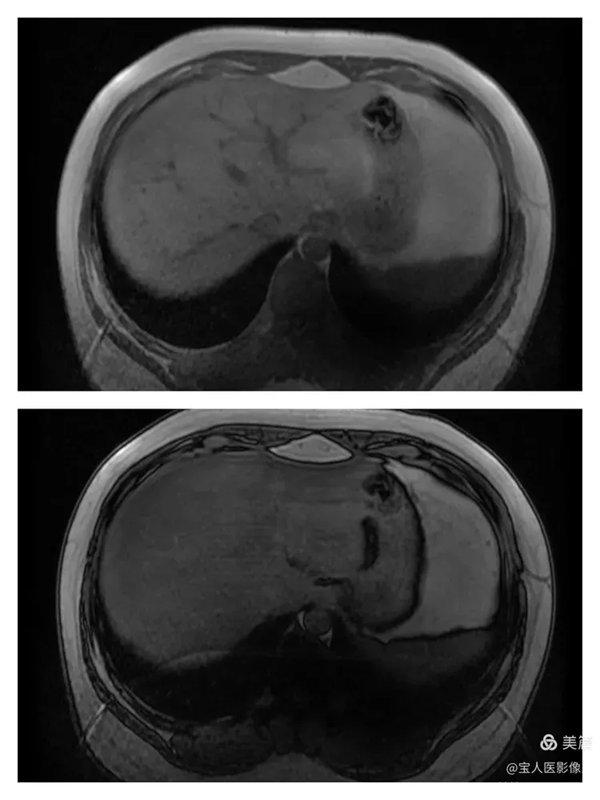

圖3

抑脂T1WI圖,軸位,肝實質信號仍呈略低信號。

圖4

同、反相位圖,肝實質在反相位上信號均勻降低。